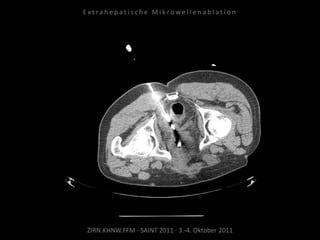

Ablation am 17.08.2010

Metastase lateral der linken Niere:

1 Nadelposition.

Metastase medial des linken

Musculus iliacus: